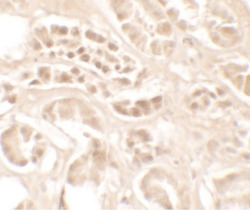

Immunohistochemistry

LS-C201117 IHC